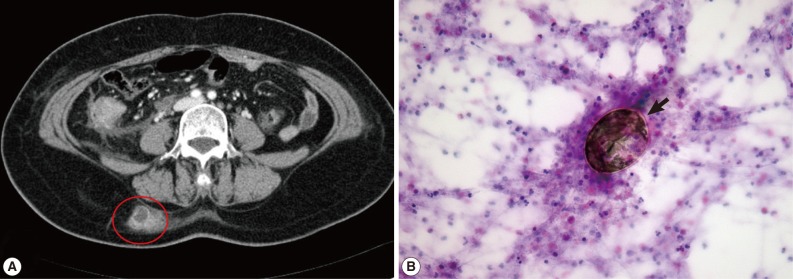

A 58-year-old woman visited our hospital for evaluation and treatment of the right flank pain over 4 days (August, lived in Namwon, Jeollabuk-do). Her vital sign was stable and physical examination revealed no specific signs. Laboratory findings showed no abnormalities, except eosinophilia (14.6%). Abdominal CT revealed localized abscess in the subcutaneous layer of the right back (Fig. 2A). Fine needle aspiration cytology (FNAC) showed the eggs of P. westermani with eosinophil-dominant inflammatory cells (Fig. 2B). ELISA (performed at Seoul Medical Institute) was positive for antibodies against P. westermani in the serum (0.69). Retrospective history results revealed that she had frequently consumed 'Kejang', which was prepared using freshwater crabs. On the basis of these findings, she was treated with praziquantel (25 mg/kg, 3 times daily for 2 days) and her right flank pain was resolved after treatment.

The diagnosis of paragonimiasis can be made based on detection of characteristic eggs in the stool, tissues, sputum, or pleural fluid, like our cases. However, the detection procedures in the tissues may be invasive, especially in the abdominal cavity. Thus, ELISA is commonly used for the immunodiagnosis of paragonimiasis, as the overall sensitivity and specificity of the assay were reported to be 90.2% and 100%, respectively [1]. However, ELISA can be used only based on clinical suspicion, which should be made in cases of eosinophilia, with the history of consumption of freshwater crabs or crayfish. Abdominal paragonimiasis may be confused with other abdominopelvic inflammatory diseases, particularly peritoneal tuberculosis (mainly granuloma formation), and peritoneal carcinomatosis [6,7]. In this case, laparoscopic exploration and biopsy can be a useful diagnostic tool to distinguish the difference between abdominal paragonimiasis and peritoneal tuberculosis. In case of a peritoneal nodule, which is combined with cancer, just like our patient (case 2), frozen and permanent biopsy must be done to rule out other inflammatory diseases before decision making and treatment. Also, FNAC can show the eggs of P. westermani at the abscess in the subcutaneous tissue, like our patient (case 3), and can be used as a diagnostic tool [8].